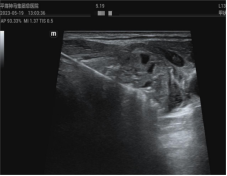

1、超聲引導(dǎo)下腫瘤的熱消融治療

熱消融技術(shù)是指在超聲實(shí)時(shí)引導(dǎo)下,將消融針插入病灶內(nèi),產(chǎn)生的高溫在短時(shí)間內(nèi)使病灶組織凝固壞死的方法。這一方法操作微創(chuàng)精準(zhǔn),效率高,范圍可控,不良反應(yīng)小,可重復(fù)性強(qiáng),實(shí)現(xiàn)了治療的微創(chuàng)、美觀、有效、安全的完美結(jié)合??剖议_展甲狀腺、乳腺、肝臟、子宮、淋巴結(jié)等多臟器實(shí)體腫瘤的熱消融治療多年,積累了豐富的臨床診治經(jīng)驗(yàn),患者受益,提高了患者的生活質(zhì)量。